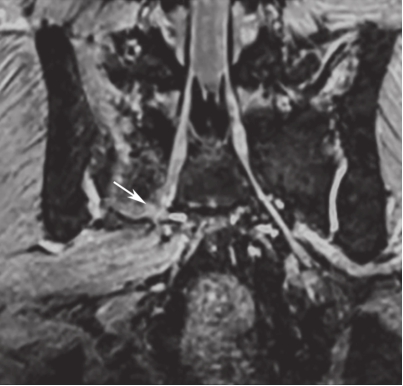

白靖平等认为用MRI扫描骶骨斜冠状面,当有骶神经损伤时,MRI图像显示骶神经周围脂肪组织消失,其直径变窄,且神经走向改变等。许道洲等则认为MRI平扫不能直接显示骶神经根的损伤,MRI SPACE-STIR序列扫描能提供三维TSE对比成像。在SPACE-STIR序列扫描图像上,在骨折周围出现下列征象时应考虑有神经根的损伤:①神经节后线状高信号走行中断,是诊断神经根损伤的直接征象,表现为神经根在骨折处呈截断征,如图2-15;②神经根走行发生改变,是诊断神经根损伤可靠的间接征象,表现为神经根自然走行弧度消失,在骨折处呈弧形受压移位改变,甚至出现成角改变,如图2-16;③神经异常肿胀增粗,是诊断神经根损伤的间接征象,表现为骨折附近神经明显较近端及远端增粗,如图2-17。

图2-17 右侧骶骨骨折,SPACE-STIR序列MRI神经成像重建

可见近骨折处S

1

骶神经肿胀、增粗,局部信号增高。